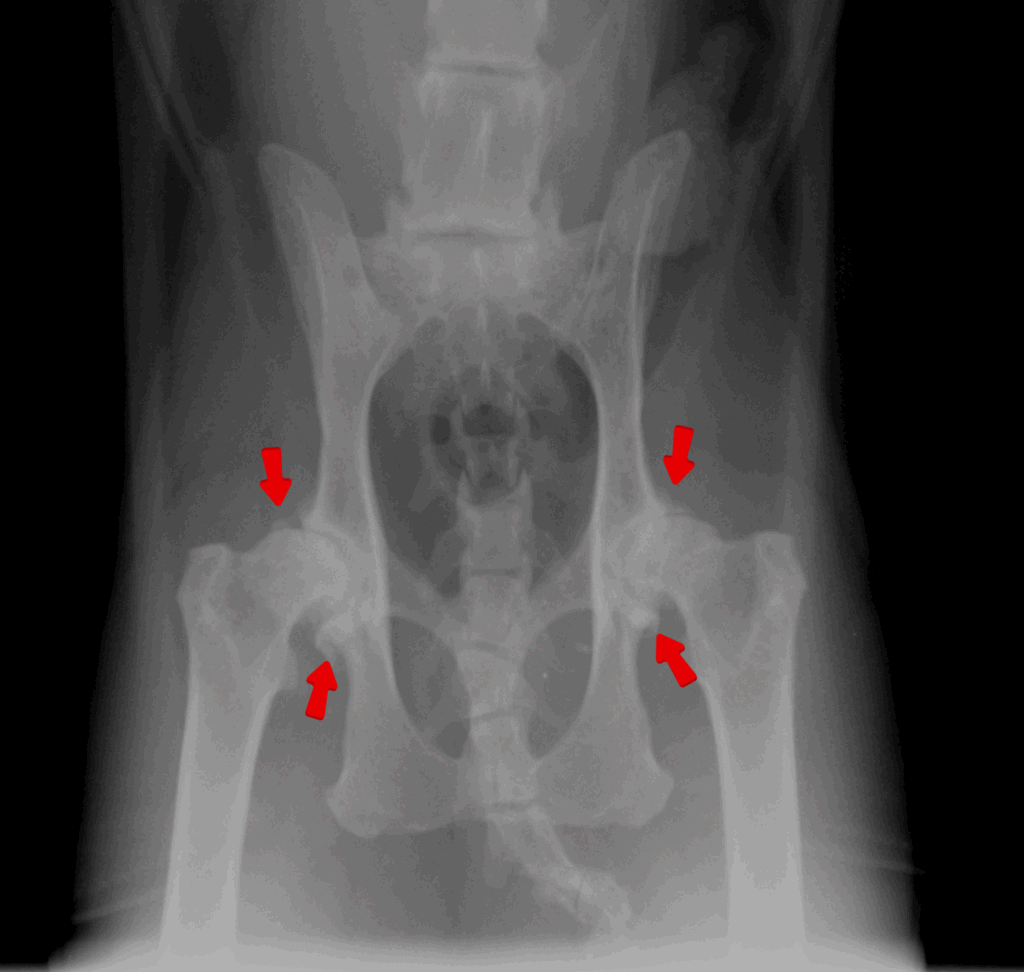

診断するにはレントゲン検査です。

関節にできた骨棘や石灰化病変を確認することで診断していきます。

特に肘関節と股関節の異常が多く認められます。